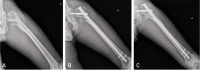

Materials and methods: Twenty-one consecutive patients with severe subtrochanteric femoral fractures who had undergone intramedullary fixation using long-PFNA II between March 2010 and March 2013 were followed-up for over 12 months. Their mean age was 64.8 years old (range, 43-85 years). Sixteen of 22 cases were high energy trauma. According to Seinsheimer's classification, 5 cases were type IV and 16 cases were type V. For radiological assessment, time to union, change of neck-shaft angle, sliding length, tip-apex distance (TAD) and leg length discrepancy (LLD) were measured. For clinical evaluation, a modified Koval index was investigated.

Results: Mean operation time was 96 minutes. An average decrease of neck-shaft angle was 4.5°. The average sliding length of the helical blade was 4.2 mm. Average LLD was 3.0 mm, and TAD was 23.0 mm. Mean modified Koval index score at final follow-up was 4.6 points. All the 21 subtrochanteric fractures healed uneventfully on an average of 24.2 weeks (range, 18-30 weeks).